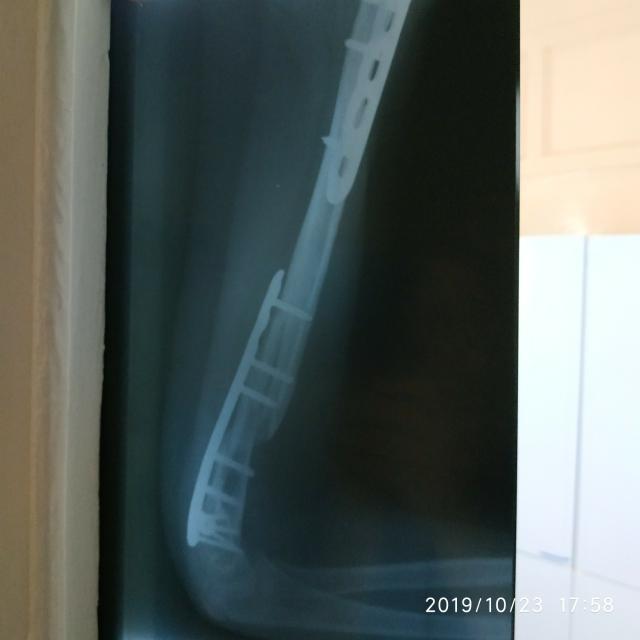

25 февраля 2019 года была проведена операция по удалению опухоли вместе с костью. На место удаленной кости поставили донорскую кость (трансплантат). После операции пройдено 8 блоков химиотерапии, специальное лечение закончено 9 августа 2019 года. Ребенок вошёл в ремиссию.

Но 20 октября 2019 года сломался трансплантат (протез). К ноябрю месяцу трансплантат сломан в двух местах. На данный момент протез разломан на 4 кусочка..